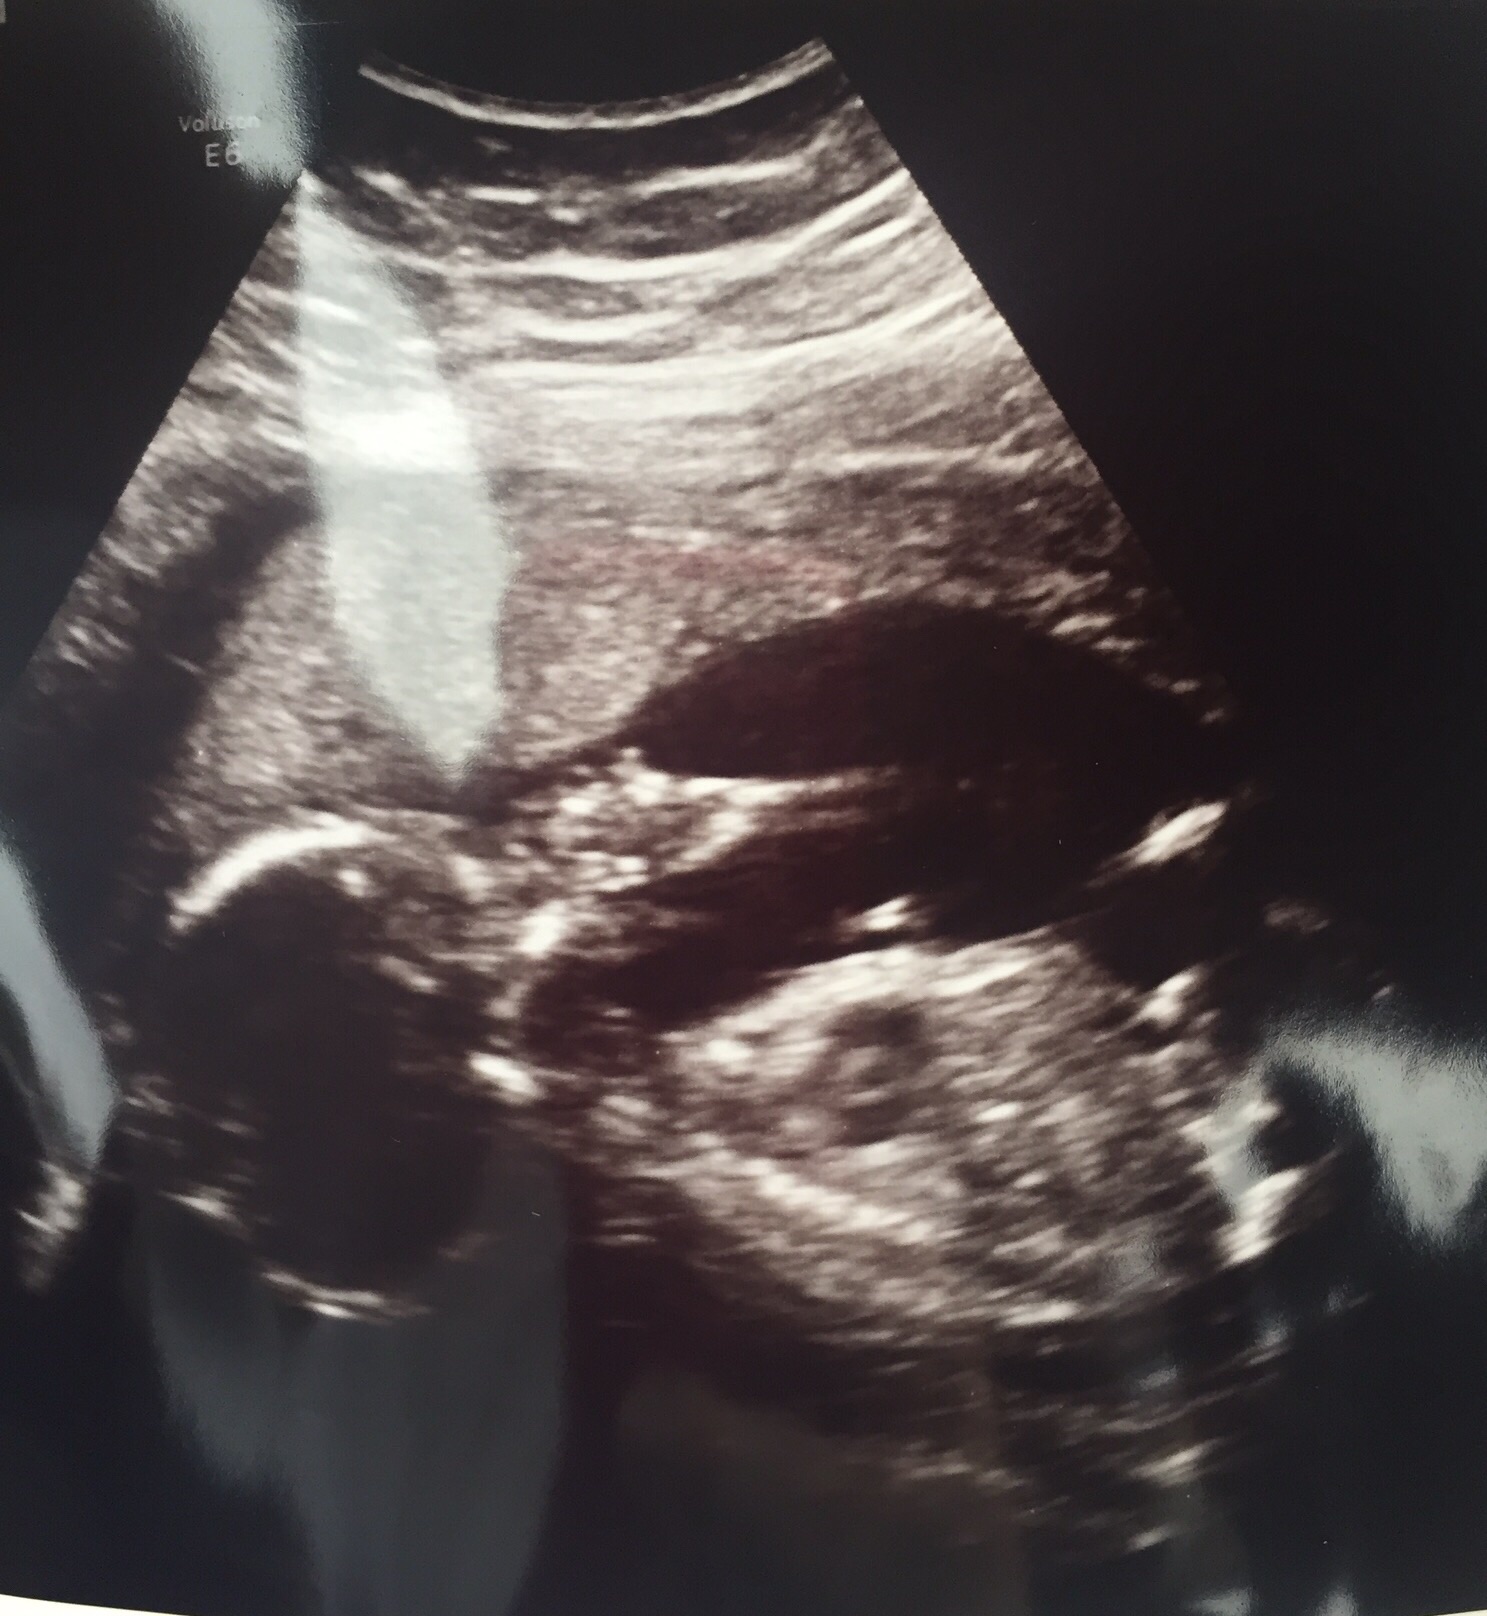

Here's a non "money shot" of our sweet boy sucking his thumb after he got done punching me!